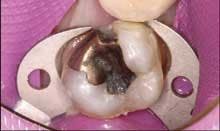

Consider the mush and recurring decay you often find under unbonded amalgams, plus the fractures under weakened cusps or brazenly dead center in sub-amalgam tooth structures. (This is common in baby boomers when canine guidance has been lost.) When I remove an old, defective, amalgam restoration, I recall turning over a rock embedded in the earth and half looking away for fear of finding something scary. Use that simile when recommending replacement of old alloys. It will help you explain the situation (Figures 3 and 4).